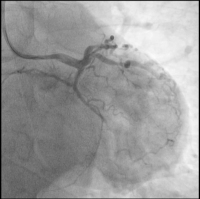

LAD

Abbildung 2: LAD: im mittleren Gefäßabschnitt langstreckig verkalkt, wirksam stenosiert